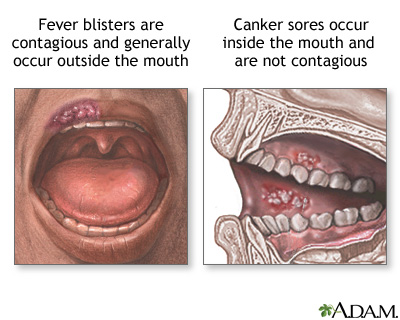

Fever blisters and canker sores. Causes, symptoms …

Medical Pictures Info – Fever Blister

Fever blister: MedlinePlus Medical Encyclopedia Image

Mouth sores. Causes, symptoms, treatment Mouth sores